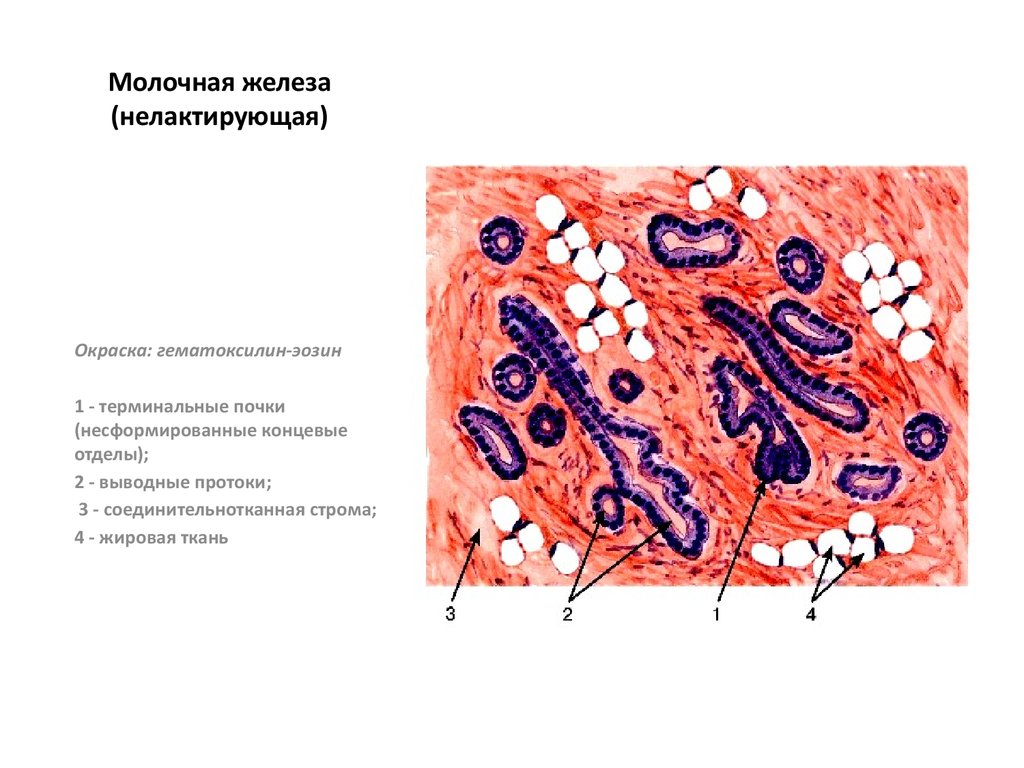

Исследование: микропрепарат молочной железы в медицине

Раздел: Снимки-откровения